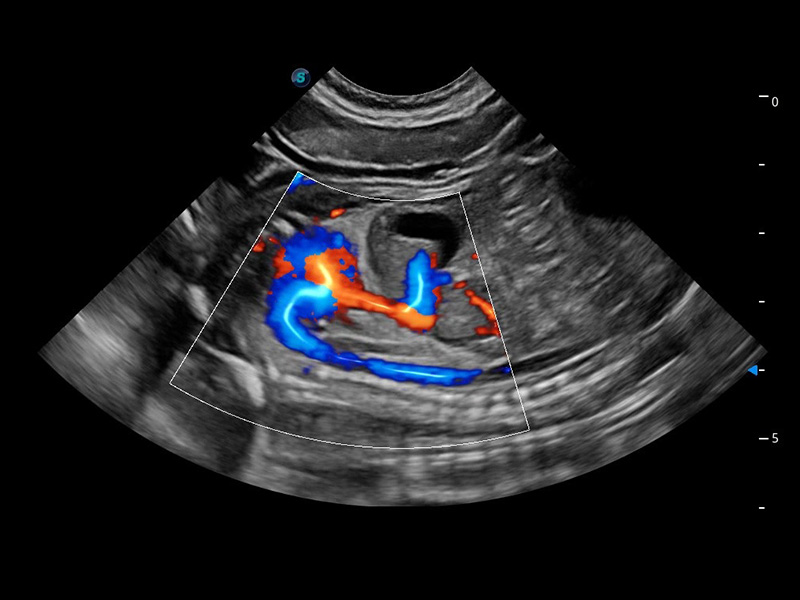

ProPet 60 作为一款高端台式动物超声设备,为动物医生的日常诊断提供了一系列贴合动物临床需求、解决临床实际问题的高级成像功能。凭借全系列高清探头,满足医生对腹部、心脏、生殖、浅表、肌骨等成像的所有需求,切实帮助您提升检查效率,提高诊断信心。

动物是人类最亲密的朋友和最值得信赖的伙伴。狗万官方网站也一直致力于探索动物专用的超声影像解决方案。 全新推出的ProPet系列,是狗万官方网站在动物超声影像智能化、专业化、精准化的一次跨越式革新。动物不能用言语来表述自己的不适,通过超声影像,ProPet系列搭建了动物医生与不同物种沟通的“桥梁”,为动物医生注入了“治愈之力”。